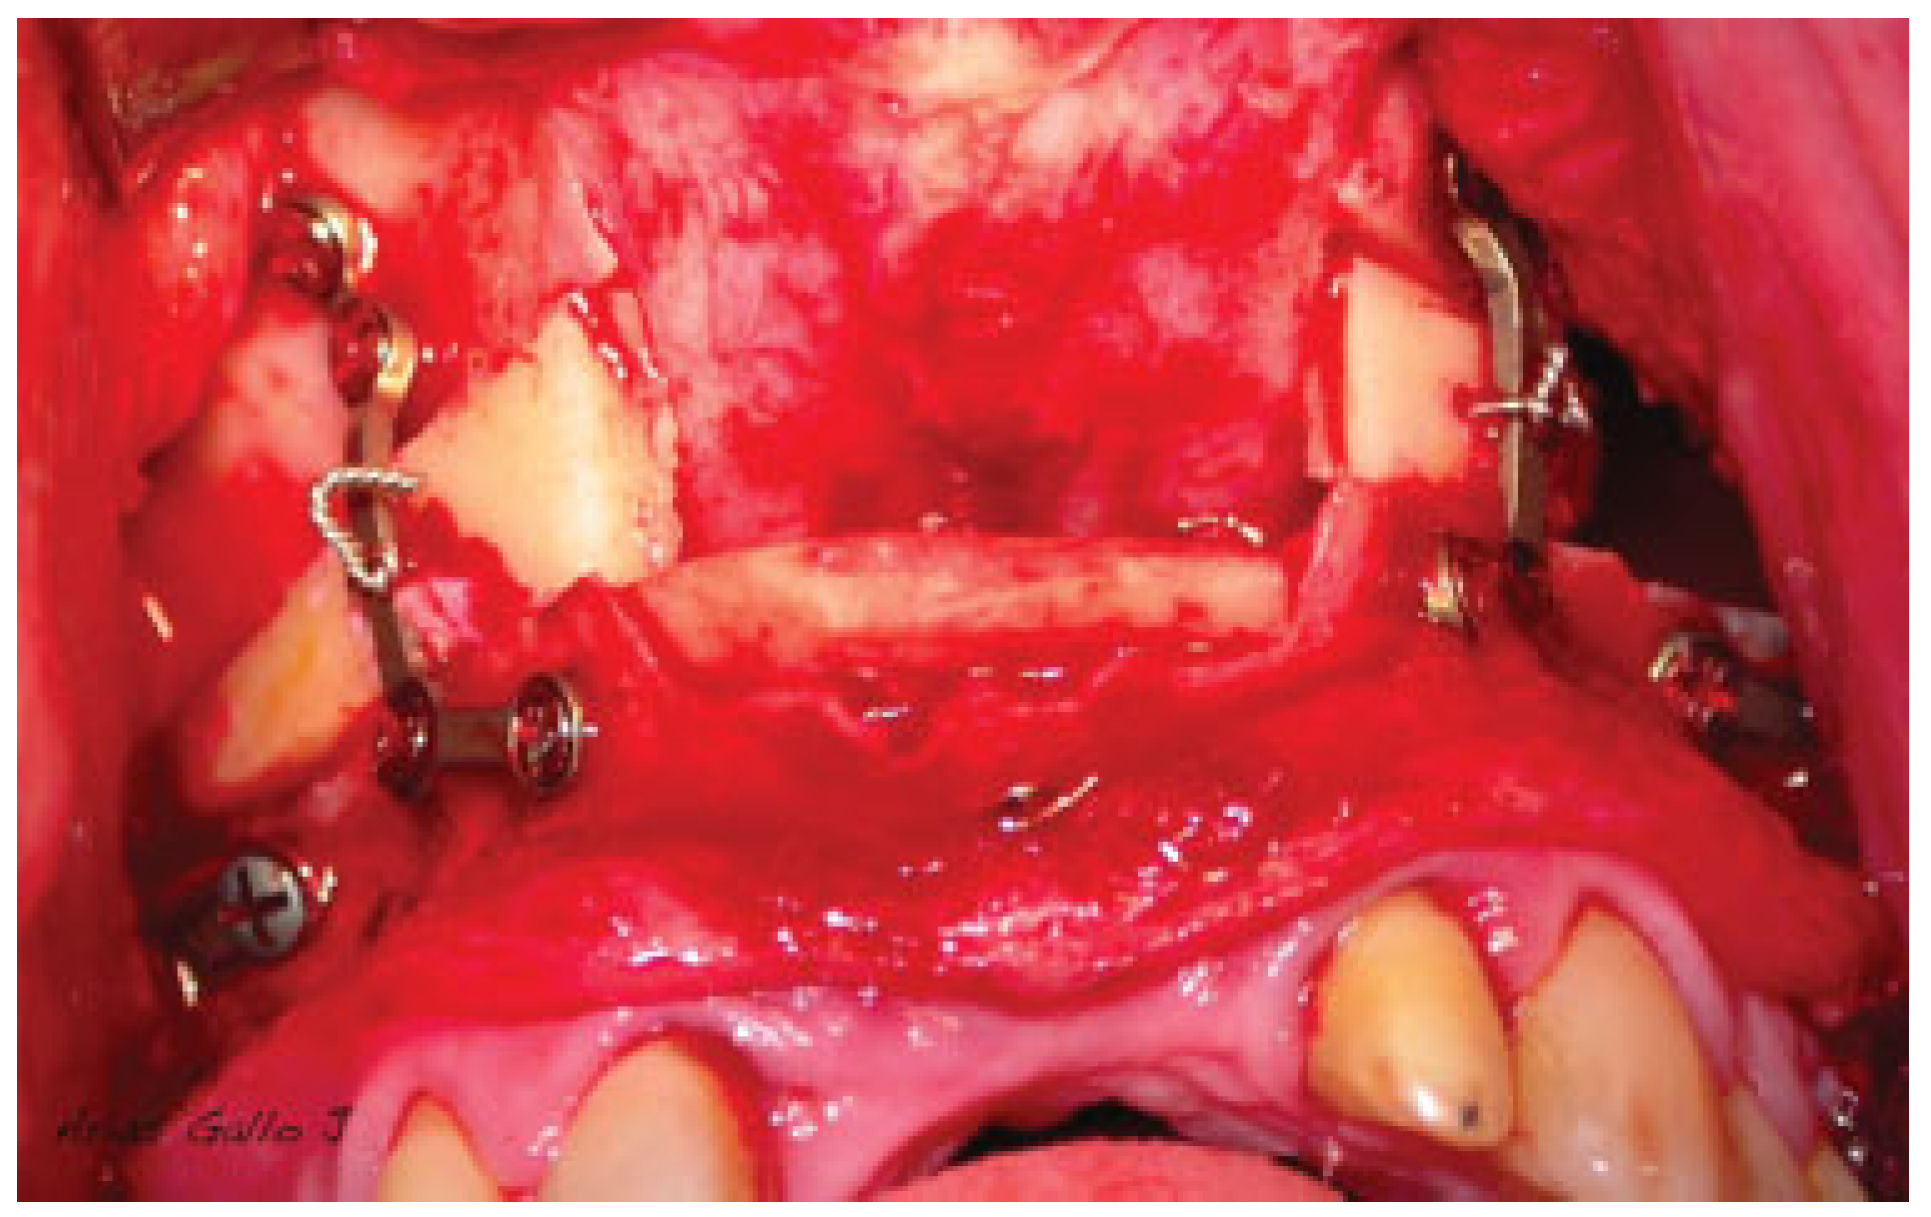

Figure 3.

Impaction and fixation of the Le Fort I osteotomy as a conventional procedure. Screw the plates to the fixed maxillary fragment.